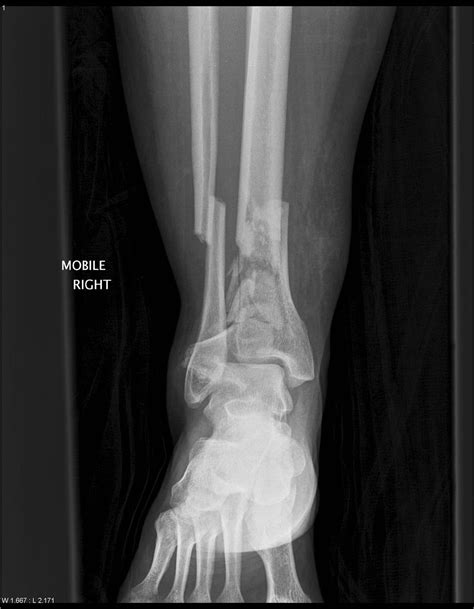

Understanding the intricacies of a *Pilon Bone Fracture* is crucial for anyone involved in orthopedic care or anyone who has experienced this type of injury. A *Pilon Bone Fracture* occurs at the distal end of the tibia, the larger of the two bones in the lower leg, and often involves the articular surface of the ankle joint. This type of fracture can be particularly challenging to treat due to its complex nature and the potential for long-term complications.

A *Pilon Bone Fracture* is a severe injury that typically results from high-energy trauma, such as a fall from a significant height or a motor vehicle accident. The force of the impact drives the talus (a bone in the ankle) upward into the distal tibia, causing a fracture. These fractures are often classified based on the pattern of the break and the extent of the damage to the surrounding soft tissues.

Type III Severely comminuted fracture with significant displacement of the articular surface and often associated with soft tissue damage.

• X-rays: Standard radiographs to visualize the fracture pattern and the extent of displacement.

• CT Scans: Providing detailed images of the bone fragments and the articular surface, which are crucial for surgical planning.